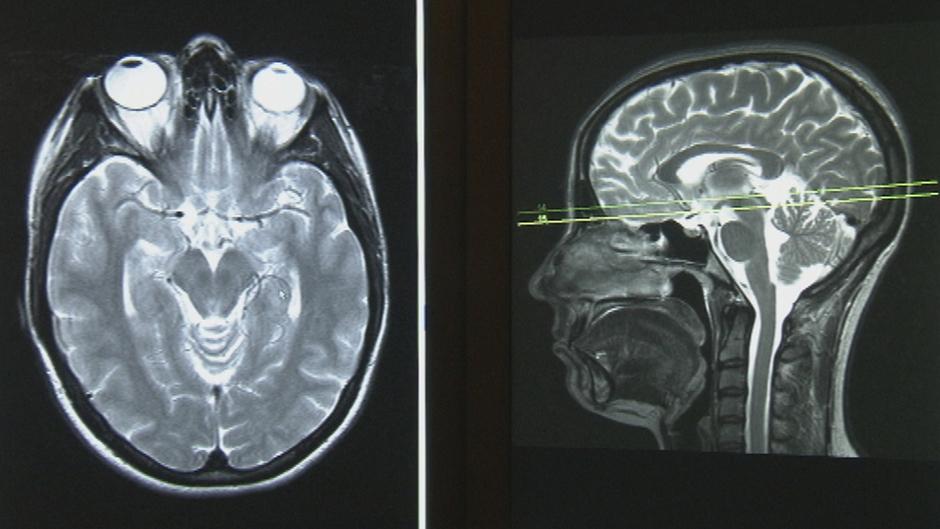

شبكة عصبونية تساعد في كشف الإصابة بكوفيد 19 في صور الأشعة السينية للصدر إم آي تي تكنولوجي ريفيو

الذكاء الصناعي يكشف أورام الثدي التي لا يميزها الأطباء Daily Sabah Arabic